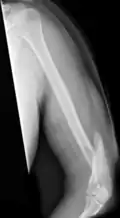

A spiral fracture of the distal one-third of the humerus shaft -